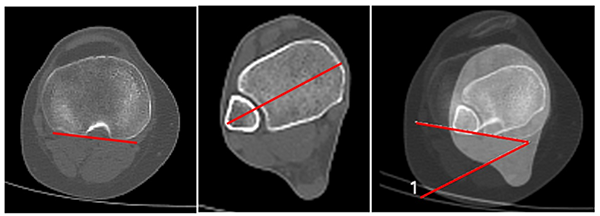

Ángulo de inclinación patelar (tilt patelar)

Esta medición se realiza en 0 y 30° de flexión de rodilla. Para el cálculo de este ángulo, se superponen las imágenes de dos cortes axiales: el corte donde se visualiza el mayor diámetro transversal de la rótula con otro corte, en el que se visualiza la escotadura intercondílea de morfología redondeada, tipo arco romano (corte de línea bicondílea). La inclinación patelar se obtendrá al medir el ángulo formado por la intersección de dos líneas: una que pasará por el centro de la rótula en su diámetro mayor, y otra que une los bordes posteriores de los cóndilos femorales (línea bicondílea). Valor normal: 10° en extensión según Galland, quien considera patológico más de 20°. La inclinación patelar varía según el ángulo de flexión de rodilla, mayor en extensión y con disminución a medida que se flexiona9, 10 (fig. 6).

Ángulo del surco

Esta medición se realiza en extensión completa de rodillas. Se utiliza el corte que represente la mayor profundidad del surco troclear, tomando como referencia las vertientes trocleares que lo forman. Se mide el ángulo formado por la intersección de las líneas que representan las vertientes trocleares. Valor Normal 138°, SD 6.9°.9 Se considera displásico un ángulo mayor a 145° (tipo A de la clasificación de Dejour).9, 11 (fig. 8).

Figura 8: Ángulo de surco. Se forma por la intercepción en el punto más profundo del surco de las dos líneas paralelas a cada vertiente troclear. Normal: 138°.

Distancia surco-tuberositaria (surco-TAT)

Esta medición se realiza en 0 y 30°. Se superponen dos imágenes tomando de referencia dos cortes tomográficos. Uno de ellos es el corte de la línea bicondílea con otro corte que visualiza el tubérculo anterior de la tibia (TAT) en el sitio de inserción del tendón rotuliano. Se trazarán dos líneas perpendiculares a la línea bicondílea, una a través de la mayor profundidad del surco troclear y otra en el centro de la inserción del tendón rotuliano sobre TAT. Se determinará la distancia surco-TAT, en milímetros, entre estas dos líneas. Valor normal: 12 mm, se considera patológico más de 20 mm.9, 11 Camathias encontró en su estudio un valor promedio de 7.8 mm en 0° y 3.9 mm en 30°.12 (fig. 9). Generalmente, este valor es mayor en 0° debido a la torsión externa de la tibia en últimos grados de extensión por mecanismo de tornillo fisiológico. En nuestra serie de trescientas sesenta rodillas evaluadas en pacientes con dolor patelofemoral (descartados los casos de inestabilidad), el valor promedio de distancia surco-TAT fue: en 0° de 14.34 ± 4.21 y en 30° de flexión de 10.39 ± 4.00. Prakash encontró 9.02 ± 5.5 en grupo control versus 19.05 ± 4,8 en grupo de inestabilidad.13

Figura 9: Distancia surco-tuberositaria. Se mide con la superposición de cortes, uno a la altura del punto más profundo de la tróclea, y otro donde se visualice la inserción del tendón patelar en la TAT. La distancia surco-TAT es la que existe entre dos líneas perpendiculares a la bicondílea: una que pasa por el punto más profundo del surco troclear, y otro que pasa por el centro de inserción del tendón patelar en TAT. Se mide en milímetros. Normal: 8 a 12 mm.